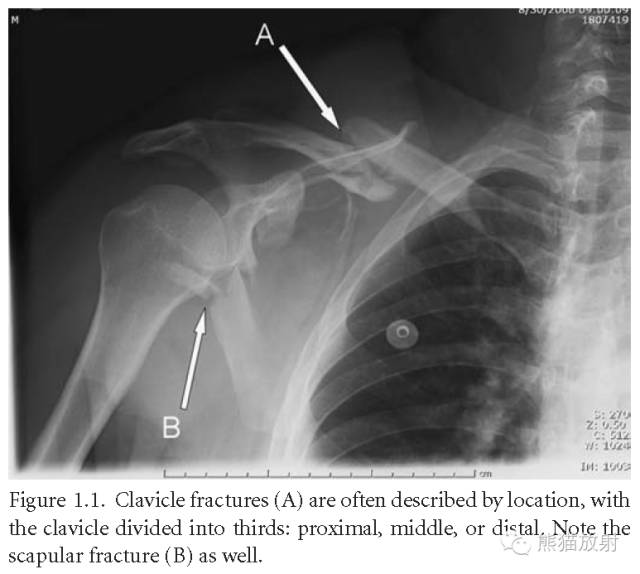

锁骨骨折(A):注意描述骨折部位(近、中、远段);肩胛骨骨折(B)。